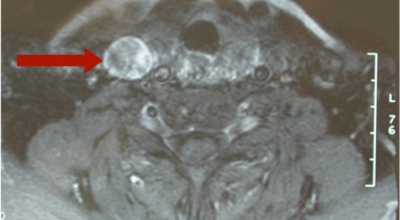

갑상선 초음파를 통하여 크기와 위치를 확인되고 있습니다. 미세침흡인세포검사라는 검사를 통하여 수술 전에 갑상선암을 알아낼 수 있어요. 또한, 혈액 검사를 통하여 갑상선 기능을 알아낼 수 있다고 하며, 갑상선 수질암의 경우 칼시토닌의 증가로 질병을 알아낼 수 있답니다. 크기가 1cm 아래로 작은 갑상선암은 간단한 초음파 검사만으로도 추적하여 검사를 할 수 있어요.